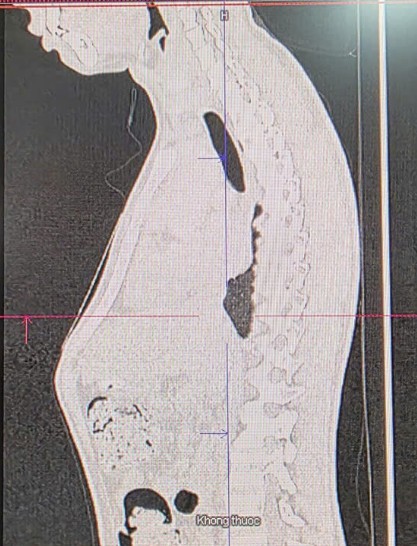

Trường hợp mới đây tại Bệnh viện Đa khoa Quốc tế Minh Anh, bệnh nhân nam 19 tuổi (T.Y.T) nhập viện trong tình trạng phần giữa ngực nhô ra rõ, gây tự ti về ngoại hình.

Theo TS.BS Lê Quang Đình, Hội Tĩnh mạch học TP.HCM, đây là dị dạng lồi ngực - bệnh thường rõ nhất ở tuổi dậy thì khi xương sụn phát triển mạnh, đẩy xương ức nhô ra trước.

Do thành ngực của bệnh nhân đã cứng, không thể nắn chỉnh bằng đai ép, ê-kíp phẫu thuật đã tiến hành mổ theo kỹ thuật Sandwich (double-bar technique) - phương pháp ít xâm lấn, thẩm mỹ cao. Bác sĩ đặt hai thanh kim loại đối kháng trong và ngoài lồng ngực, giúp chỉnh lại biến dạng và cân bằng áp lực, mang lại dáng ngực phẳng, cân đối.